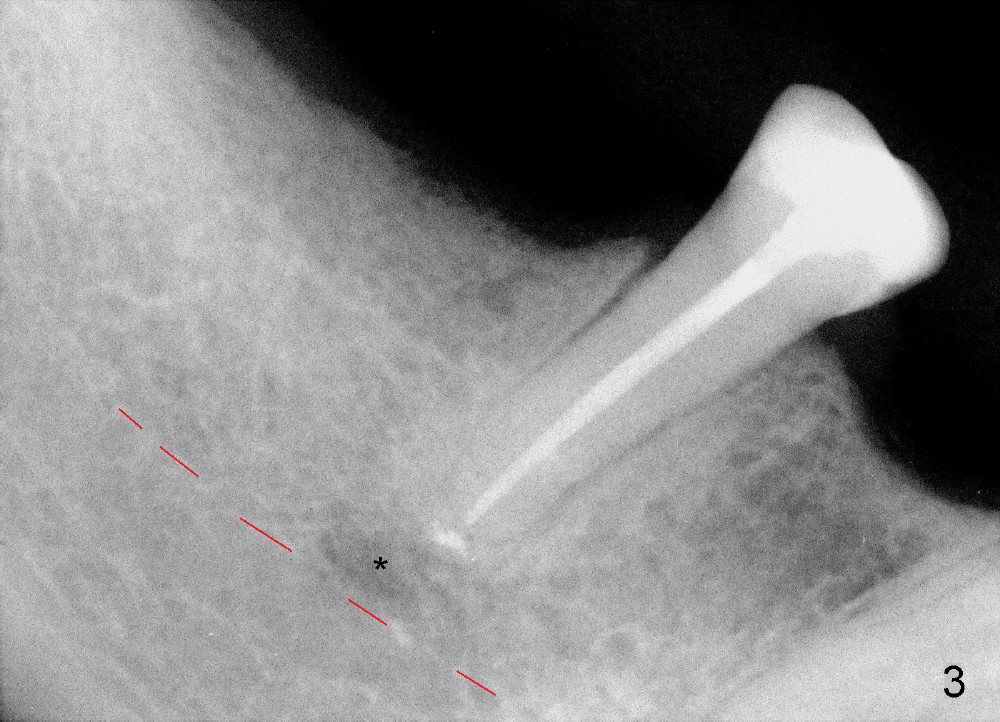

A 57-year-old lady has a lower partial. One of the abutments fractures (Fig.4). The apex is close to the presumably mental loop (Fig.3*; red dashed line: upper border of the inferior alveolar canal).